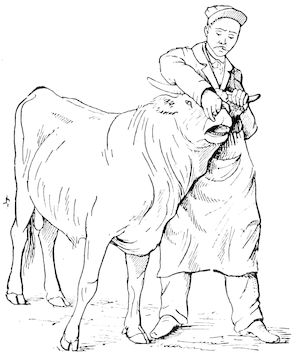

Fig. 1.—Rachitis in a young goat.

Fig. 1.—Rachitis in a young goat.